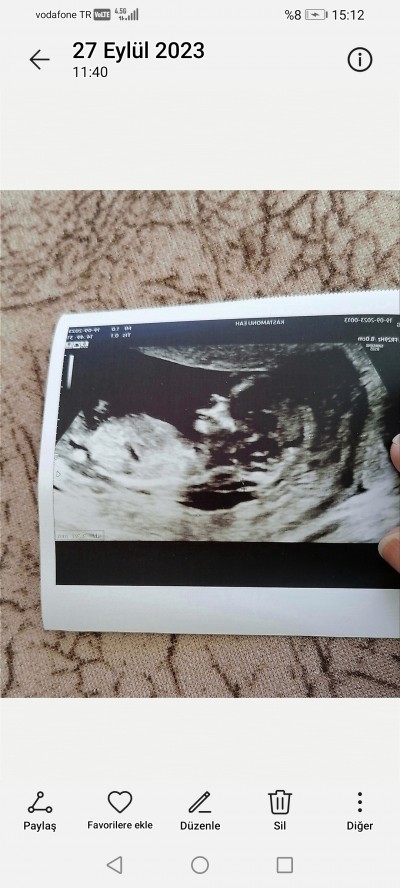

13 haftalık 3 gunluk doktora cinsiyet hakkında hiçbirsey söylemedi merak ediyorum nub teorisi dogruluk payı cok oldugunu duydum sizce ne olabilir cinsiyeti

image